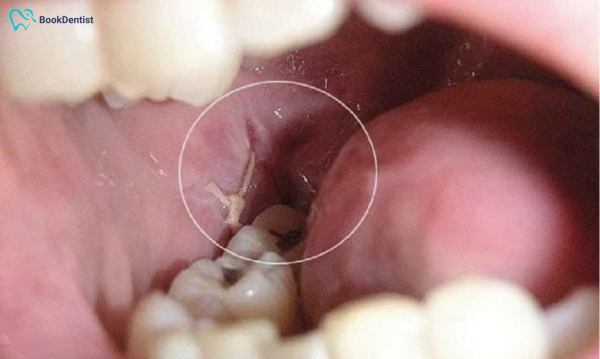

Xuất hiện mủ

Mủ tại vị trí nhổ răng khôn là dấu hiệu rõ ràng của nhiễm trùng. Việc vi khuẩn xâm nhập vào vết thương và không được xử lý kịp thời có thể dẫn đến tình trạng viêm mô xung quanh, tạo mủ.

Trường hợp nhổ răng xong xuất hiện màng trắng sau khi nhổ răng nghĩa là dấu hiệu tốt. Màng trắng sau khi nhổ răng là mô hạt, mô mạch máu, hoặc cục máu đông, giúp ngăn chặn vi khuẩn và làm nền tảng cho sự phát triển của mô xương mới. Tuy nhiên, nếu màng trắng kèm theo các triệu chứng như đau nhức dữ dội, mùi hôi trong miệng, hoặc sốt, đó có thể là dấu hiệu của ổ răng khô hoặc nhiễm trùng và bạn cần đi khám.